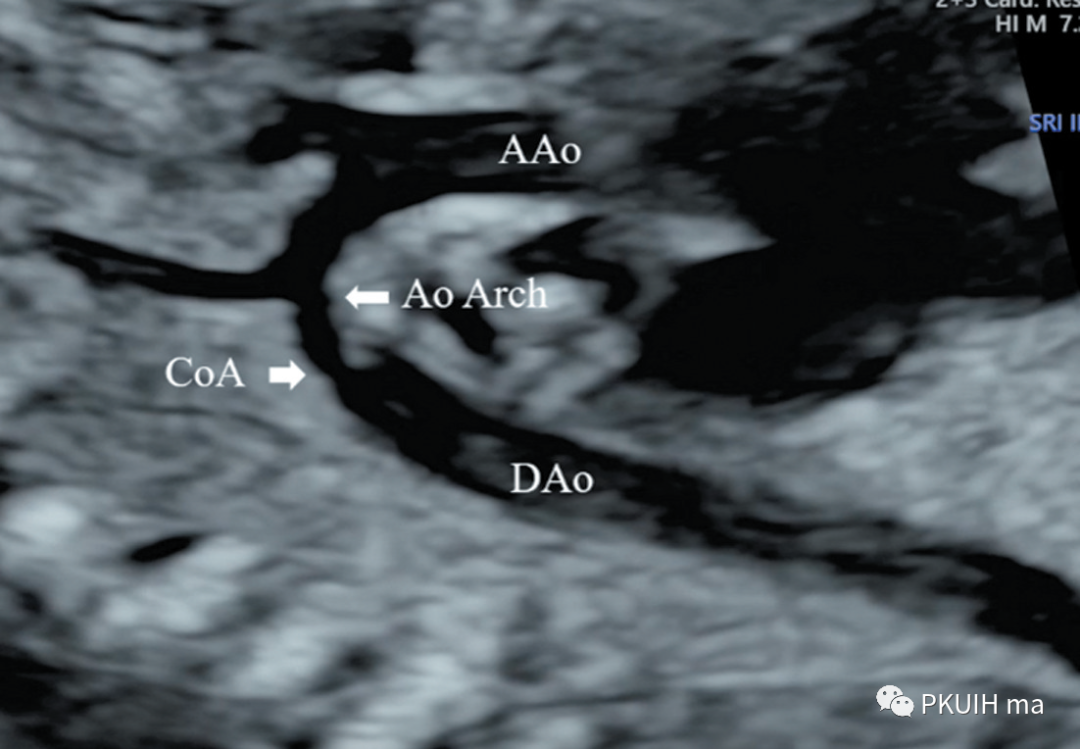

再次可以通过主动脉弓长轴、三血管气管切面观察,主动脉弓长轴切面显示主动脉横弓细窄。主动脉峡部内径与动脉导管内径比值减小与CoA高度相关,峡部与动脉导管内径比≤0.74时发生CoA风险明显增高。同时主动脉弓上的分支血管间距离增大,颈动脉与左锁骨下动脉之间的距离越远,缩窄的可能性就越大。上图CoA主动脉弓长轴切面显示主动脉峡部细窄(AAo:升主动脉,DAo:降主动脉,Ao Arch:主动脉弓,箭头所示为缩窄部位)上图 CoA胎儿三血管气管切面,图像显示主动脉峡部明显细窄,内径1.0 mm (Duct:动脉导管;Isthmus:主动脉峡部)